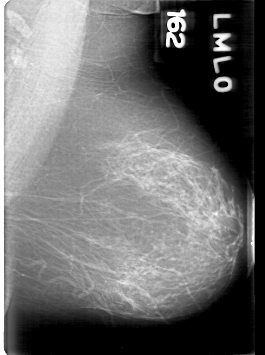

D_4094_1.LEFT_MLO

LEFT_MLO LINES 5311 PIXELS_PER_LINE 3961 BITS_PER_PIXEL 12 RESOLUTION 43.5 NON_OVERLAY